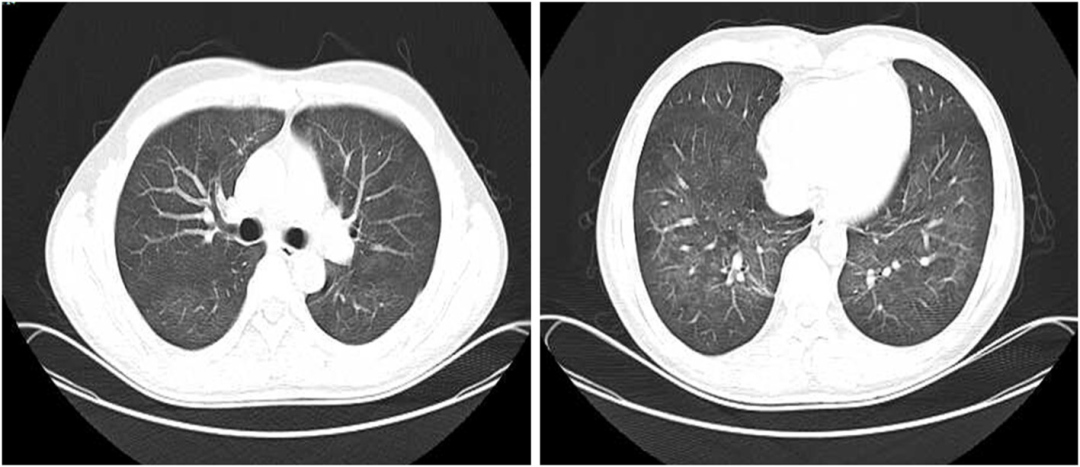

接受静脉注射头孢曲松(2g,每日一次)治疗2周,口服磺胺甲恶唑-甲氧苄啶(0.96g,每日两次)。治疗一周后胸痛缓解。治疗6周后,胸部CT扫描显示肺空洞消失,只留下少量斑片状浸润。胸膜增厚情况有所改善(图2)。

图2:治疗6周后胸部CT显示空洞消失,仅留下少量斑片状浸润,胸膜增厚改善